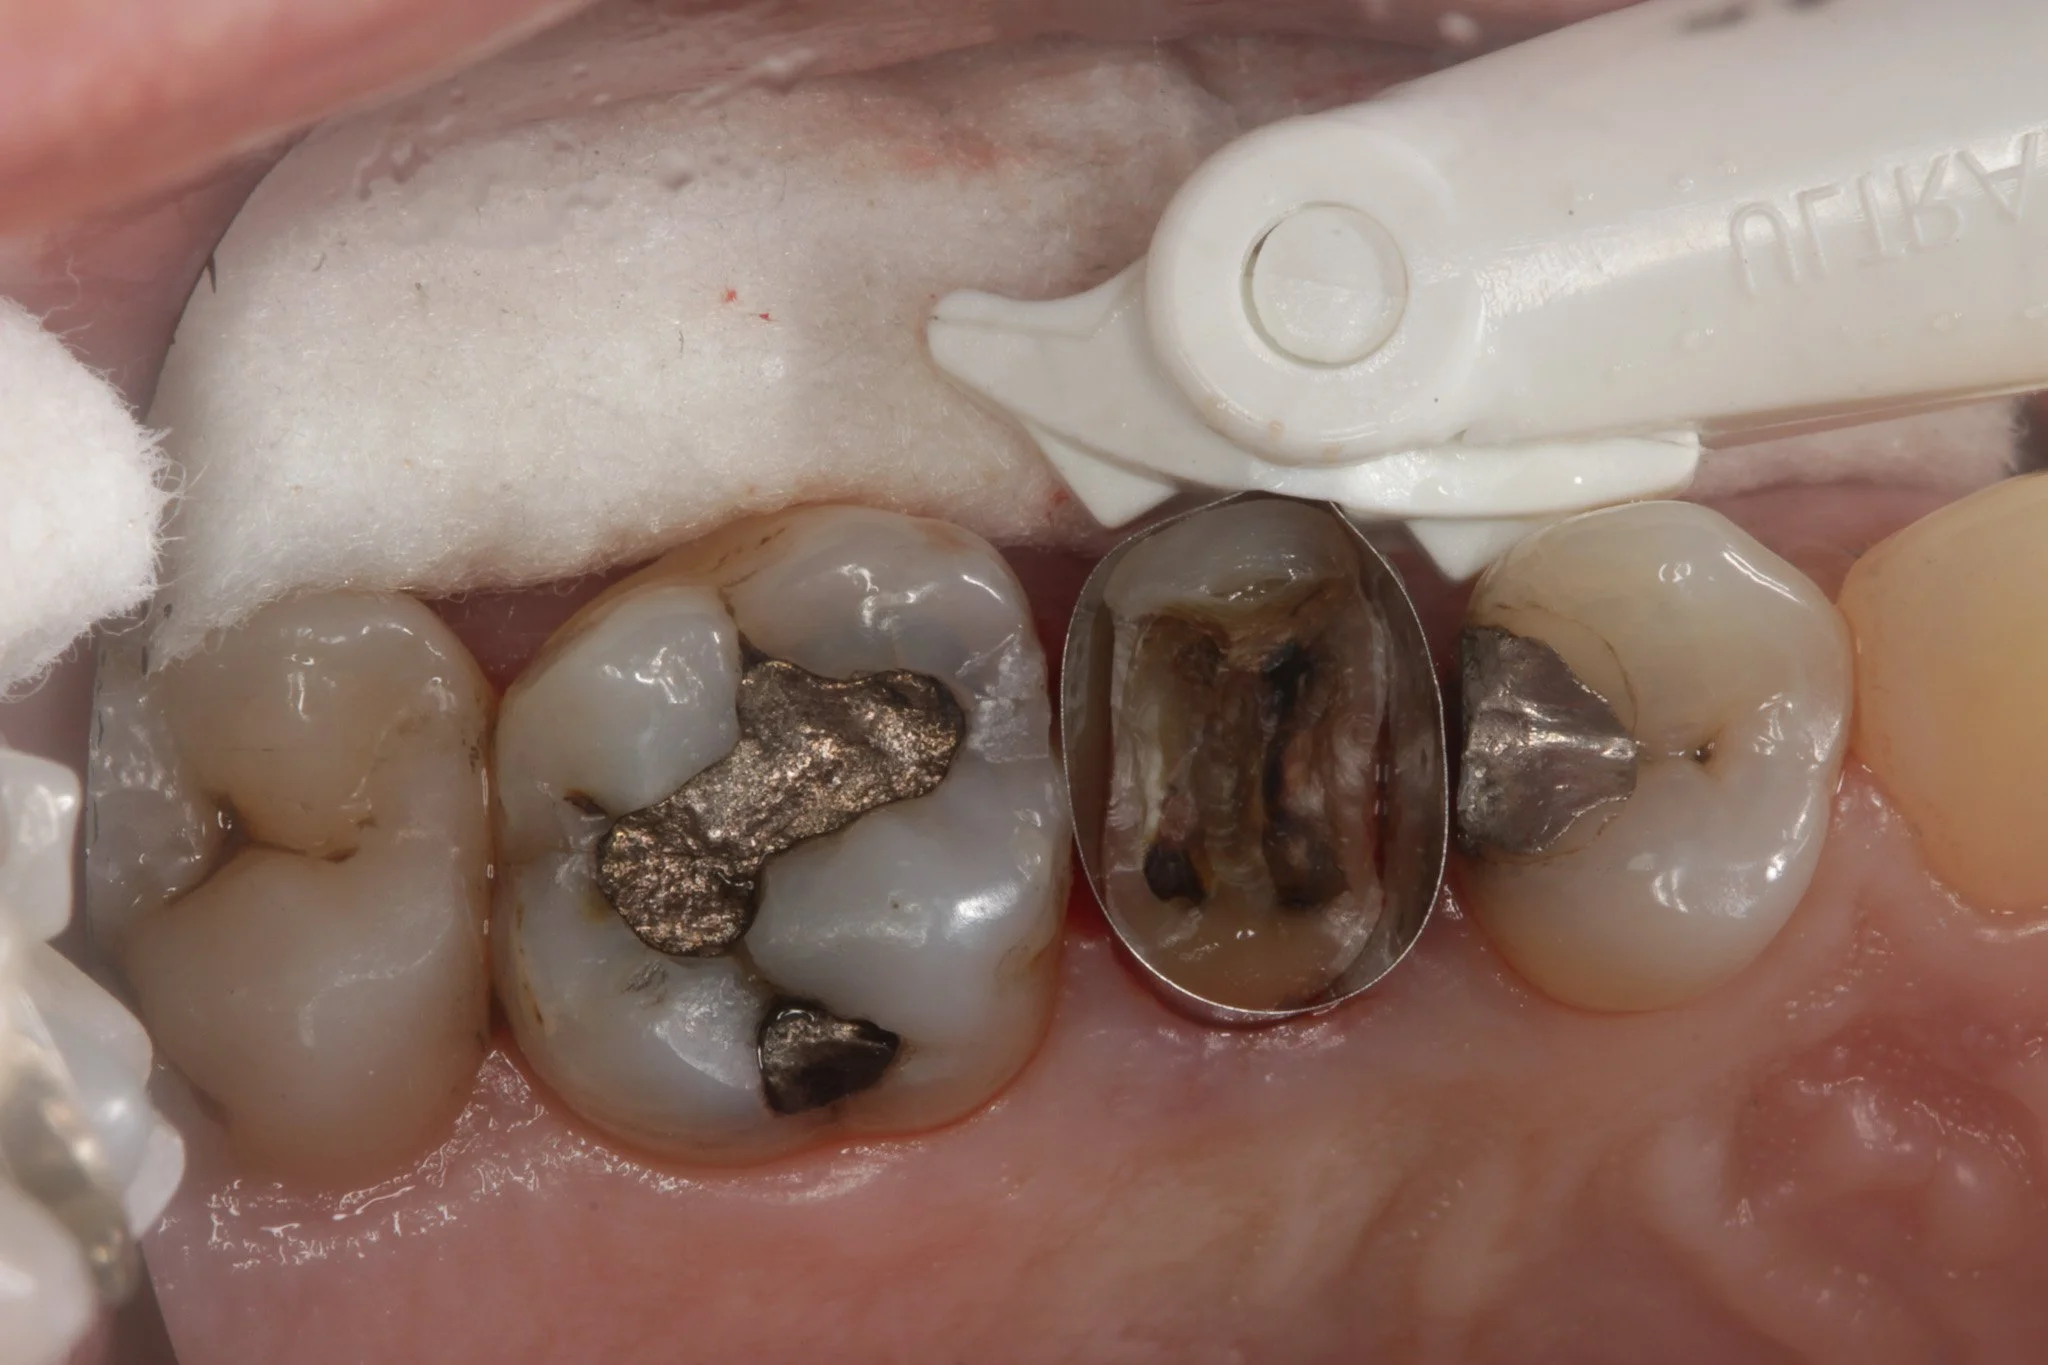

Isolating the margins with a matrix band to keep them dry

Replacing the Filling

In many cases, the simplest solution is to remove and replace the filling. This allows the dentist to:

• Correct the shape and contour

• Remove any overhangs

• Create a smooth margin that is easier to clean

For more accessible areas, this is often very effective and minimally invasive.